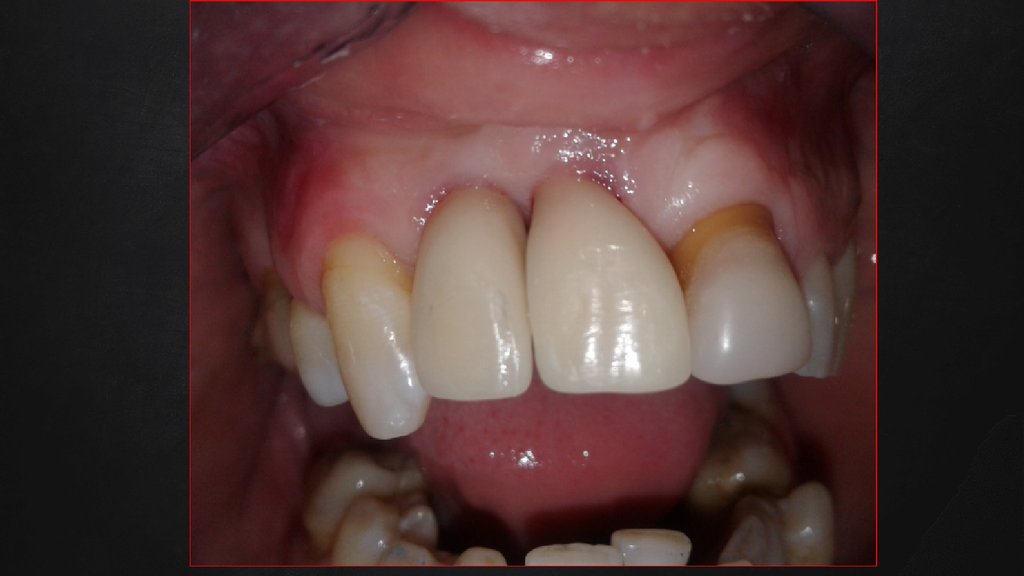

Клиническая картина до проведения имплантации.

После периода заживления во время планирования дальнейшего лечения был сделан анализ факторов риска, которые

могли повлиять на качество выполненного лечения с эстетической и морфофункциональной точек зрения.